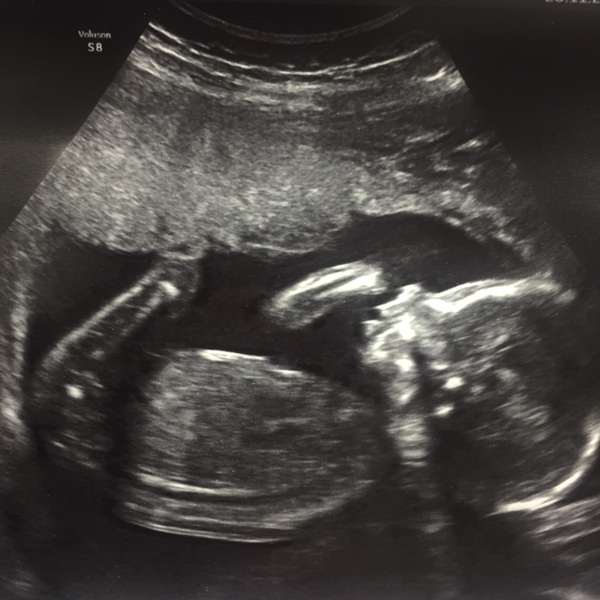

I'm also team blue. Had our scan today and measuring a few days ahead again. Also looks like he has long legs like his daddy as they're measuring 21 wks vs the rest of the body at 20wks. Beyond excited now and struggling to focus at work Grin

Lovely scan news and great pictures. My scan is on Friday, can't wait! We will be team yellow, but I agree that boys names are harder than girls.